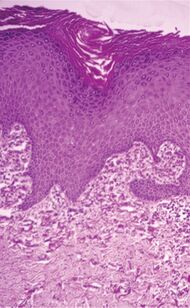

| Elastosis perforans serpiginosa | Degenerated elastic fibers and transepidermal perforating canals (arrow in image points at one of them)[9] | |